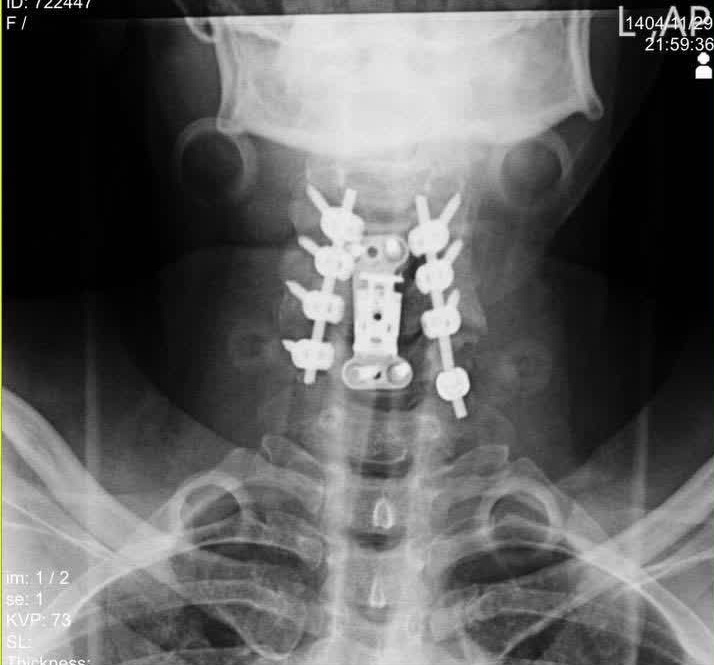

دکتر محمدی ادامه داد: ۷۲ ساعت پس از جراحی اول، بیمار مجدداً به اتاق عمل منتقل شد. در مرحله، تیم جراحی با انجام «لامینکتومی» از مهره سوم تا ششم (C3-C6)، فشار را از روی بخش پشتی نخاع برداشتند و با استفاده از سیستم «پیچ و راد» (Screw and Rod) در ۸ نقطه مختلف، پایداری کامل ستون فقرات بیمار بدست آمد.

تمام مراحل عمل تحت نظارت دستگاه پیشرفته نورومانیتورینگ انجام شد.